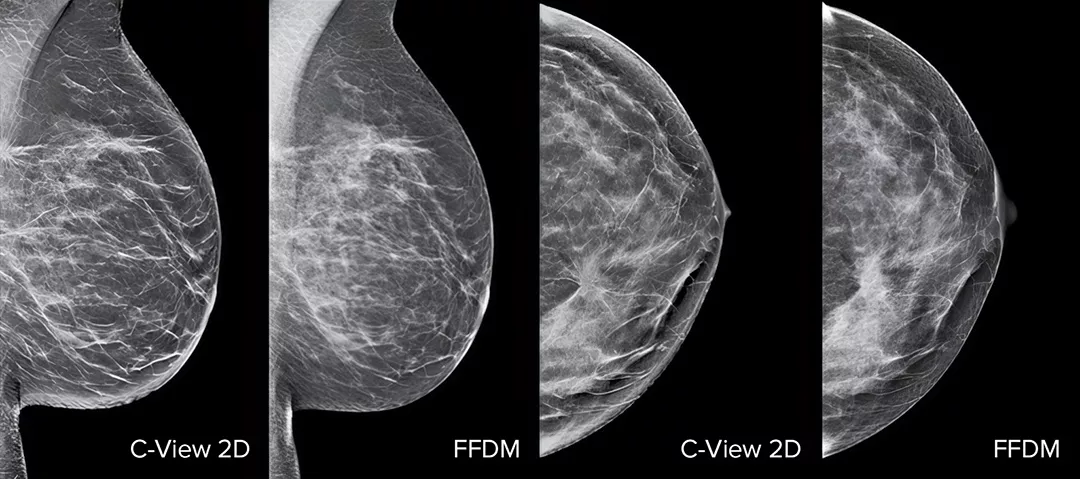

Steigern Sie die Leistung Ihrer Brustkrebs-Vorsorgeuntersuchungen1-4 mit der C-View Software und sofort erstellten synthetischen 2D-Bildern. Diese sorgt nicht nur für eine höhere Detailgenauigkeit und schnellere Befundung, sondern reduziert auch die Strahlendosis für Ihre Patientinnen. C-View 2D-Aufnahmen sind klinisch erprobt3,5 und von der FDA zugelassen, um im Rahmen der Tomosynthese-Untersuchung die FFDM-Aufnahmen diagnostisch zu ersetzen.

Anormale Strukturen, Raumforderungen und helle Flecken, die häufig bei Mikroverkalkungen auftreten, sind auf dem C-View 2D-Bild besser zu erkennen als auf herkömmlichen FFDM-2D-Bildern oder Tomo-Schnittbildern.4,6-9

C-View 2D-Aufnahmen sind klinisch erprobt3,5 und von der FDA zugelassen, um im Rahmen der Tomosynthese-Untersuchung die FFDM-Aufnahmen diagnostisch zu ersetzen. Die Bilder dienen auch als Navigationshilfe für die Durchsicht der Tomosynthese-Schichtaufnahmen. Studien zeigen, dass die niedrig dosierte 3D-Mammografie-Untersuchung invasiven Krebs im Vergleich zu reinen 2D-Verfahren früher findet und gleichzeitig die falsch-positiven Befunde reduziert.4,5,7

Anormale Strukturen, Raumforderungen und helle Flecken, die häufig bei Mikroverkalkungen auftreten, sind auf C-View 2D-Aufnahmen besser zu erkennen als auf einem herkömmlichen FFDM-2D-Bild oder einer Tomo-Schicht.4,6-9